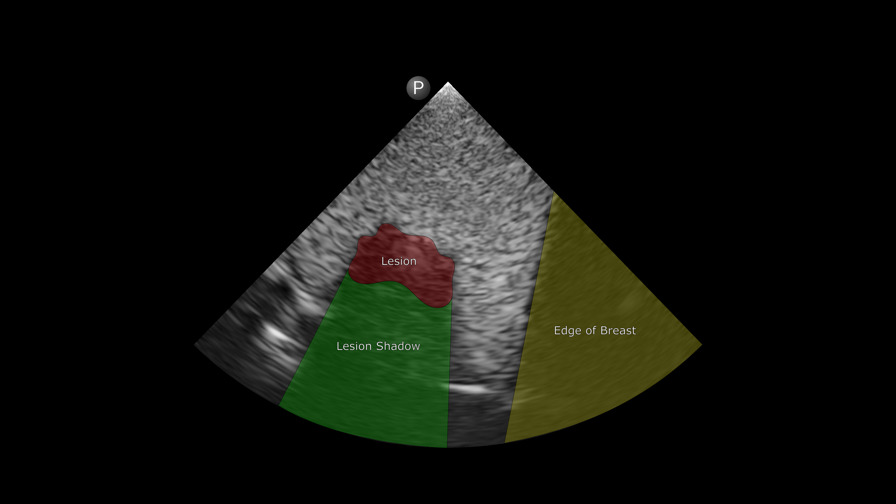

Breast lesion labeled

Using Digital Anatomy materials and a deidentified patient MRI scan, the research team wanted to create an ultra-realistic breast tissue model. From the GrabCAD software’s anatomical preset library, they chose Encapsulated Subcutaneous Fat to replicate the tissue of the breast itself and Solid Internal Organ 6 for the tumor.

With point of care ultrasound (POCUS), the team was able to visualize the lesion right away, but when they transitioned to the ultrasound suite with a more powerful transducer, they discovered that they needed to lower the frequency to match the POCUS settings. This adjustment ensured that the printed model would produce signals similar to those from actual human breast tissue.

“What seems to matter most is the difference between the object that you’re putting inside the material and the bulk material,” says Csordas. “Subcutaneous Fat and Solid Internal Organ 6 work well in contrast.”

“The two materials have a really nice echogenic interface,” adds Dr. Cox.